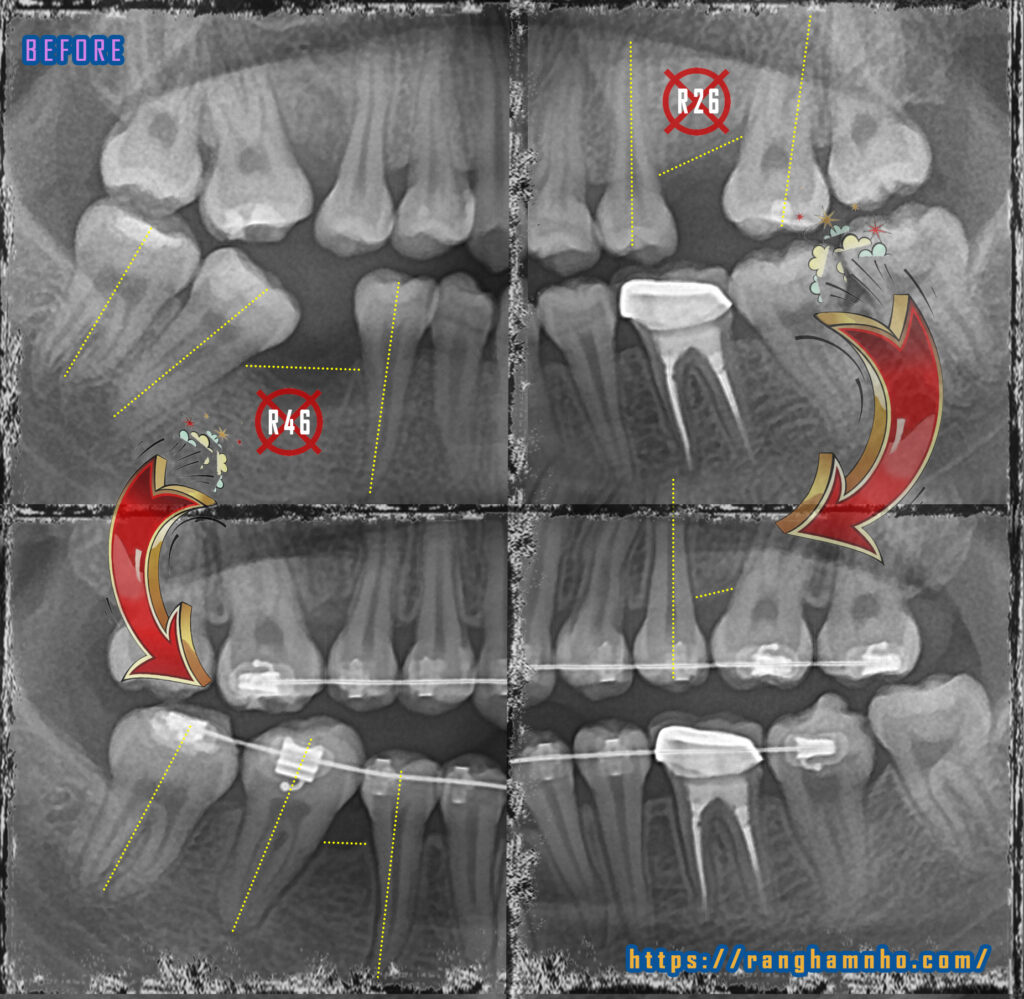

Không phải trường hợp nào mất răng cũng cần trồng răng giả. Trong nhiều trường hợp, có thể di gần răng 7 vào thay thế răng 6 mất, di gần răng 8 vào vị trí răng 7. Đánh giá và tiên lượng thời gian di gần thay thế răng phụ thuộc rất nhiều yếu tố: tình trạng chân răng 7 và răng 8 phía xa, mật độ xương tại vị trí răng 6 mất, mức độ tiêu xương tại vị trí răng 6 mất, khớp cắn….

Một case di gần thành công còn phụ thuộc cả sự hợp tác của bệnh nhân bởi thời gian điều trị lâu và khó nhất là chân răng phải dịch chuyển tịnh tiến chứ không phải nghiêng gần thân răng.